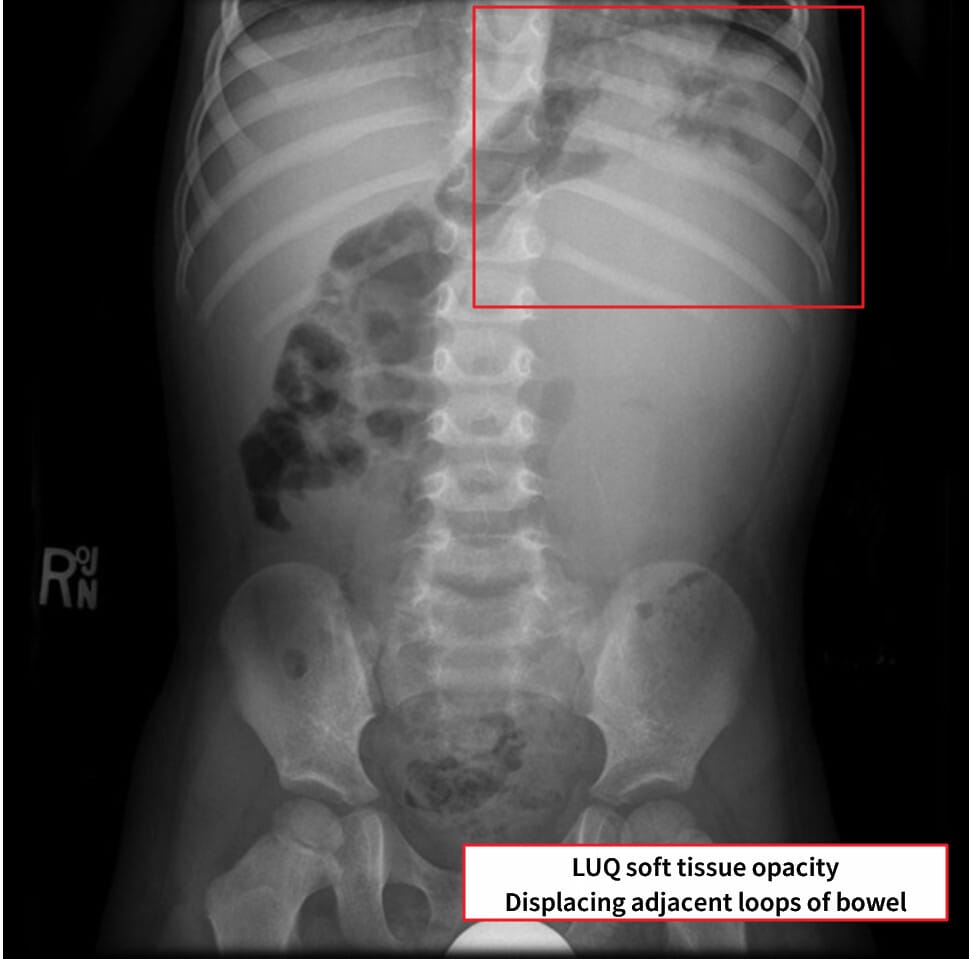

복부 X-ray 소견

X-ray는 비특이적이지만, 종양이 커지면서 복강 장기 위치를 밀어내는 변화를 간접적으로 확인할 수 있습니다.

| 🟦 복강 내 장기 밀림 (mass effect) |

| 우측 대형 종괴로 인해 장이 좌측으로 밀리며, 복부 전체가 팽창되어 보일 수 있습니다. |

| 🟦 석회화는 드묾 |

| Wilms tumor는 대부분 석회화를 동반하지 않기 때문에 X-ray에서 종괴의 윤곽은 불분명할 수 있습니다. |

Gaillard F, Wilms tumor. Case study, Radiopaedia.org (Accessed on 24 May 2025) https://doi.org/10.53347/rID-5957